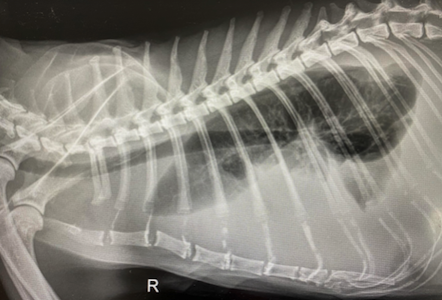

6. Інструментальні методи (УЗД, рентген, МРТ)

Можуть допомогти виявити:

- асцит (черевний, плевральний або перикардіальний),

- лімфаденопатію, особливо мезентеріальних вузлів,

- збільшення органів (печінки, селезінки, серця),

- гранульоматозні зміни або маси.

Як і в аналізах крові, ці зміни не є унікальними для FIP.